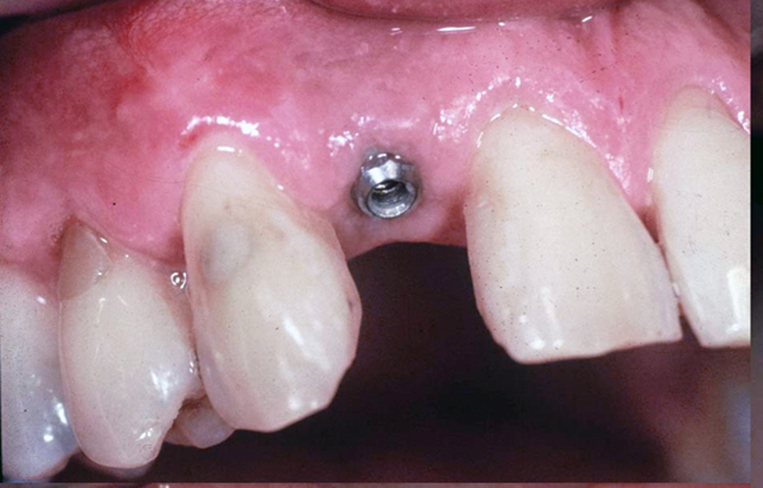

Flapless Implant Placement: Key Details

Definition: Implant placement without lifting gum tissue, minimizing invasiveness.

• Guided Access: Small punch made for direct bone access.

• Implant Placement: Implant inserted through minimal access with high precision.

• No Drilling: Avoids drilling, preserving bone and reducing trauma.

• No Flap Elevation: Eliminates soft tissue detachment, ensuring no bleeding.

• Improved Esthetics: Soft tissue contour is maintained.

Implants vs. Dental Bridges

(13 years After Placement)

“Dental implants prevent bone loss and preserve jaw strength and aesthetics.”

“Dental bridges risk gum disease, jaw shrinkage, and aging effects like wrinkles and bridge loss.”